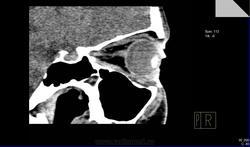

Имеется ли какая-либо орбитальная патология?

Имеется ли какая-либо орбитальная патология?Поделитесь, коллеги,своим мнением,пожалуйста!Если есть,то в глаза патология бросается?

Вот-вот!Меня тоже ничего не смутило.Я и сделал заключение:норма.В направлении ничего толкового написано не было.А почти 2 недели спустя офтальмолог мне с пеной у рта доказывает,что у пациентки отёки необъяснимые в  последнее время,а я(такой-сякой) не вижу утолщения внутренней прямой мышцы глаза!

Я присмотрелся и согласился с ней,извинился,переделал протокол,а про себя поругал за невнимательность.Потом стал присматриваться при других исследованиях(глазниц,головного мозга) к глазницам и почти у всех внутренняя прямая мышца толще и плотнее остальных мышц.

Отсюда вопрос:есть тут или нет эндокринная офтальмопатия?